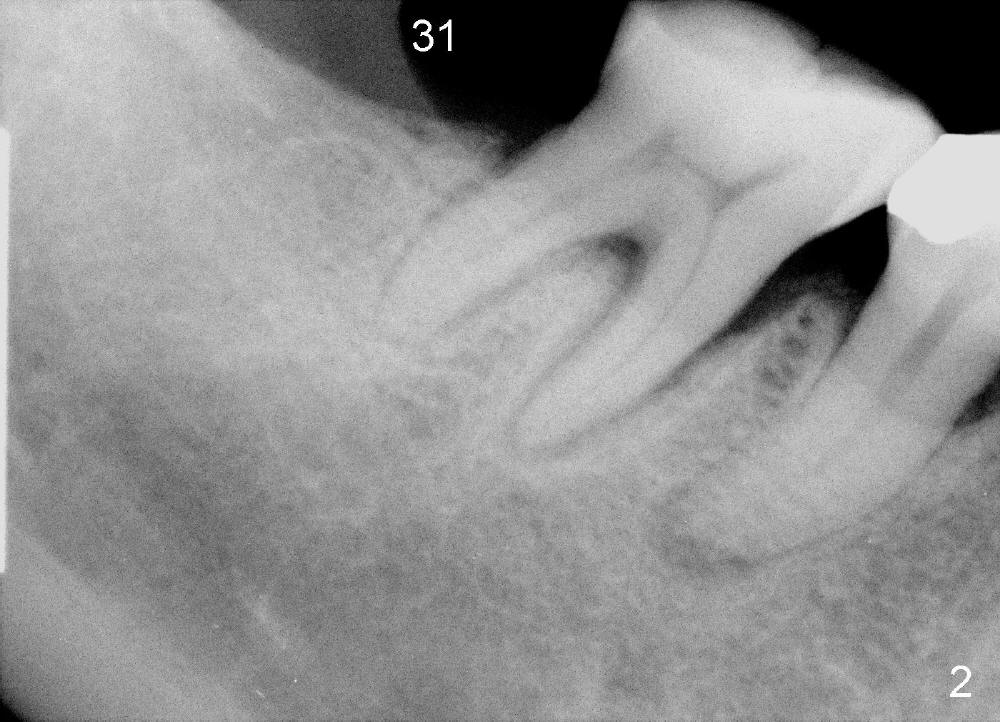

A 57-year-old lady returns for #31 implantation. The vertical edentulous space is limited, as the opposing tooth is supraerupted (Fig.1 arrow). Preop PA is critical (Fig.2), since it is used to measure the bone height (Fig.3: 12 mm). The length of the implant is expected to be 10 mm. The initial osteotomy depth is 8 mm (Fig.4); it appears that the trajectory should be adjusted. Osteotomy increases following depth and angulation adjustment (Fig.5: 4.5x10 mm drill). The submerged implant (5.3x10 mm) is placed with insertion torque approximately 35 Ncm (Fig.6). The buccal microthreads are exposed (Fig.7); to prepare for bone graft, the buccal plate is decorticated. Following placement of freeze dry mineralized allograft, collagen membrane is fixated by a healing screw (Fig.8). The incision is closed by 4-0 Chromic gut sutures and perio glue (Fig.9).